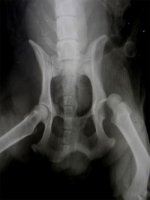

Для более точной оценки состояния потребуется рентгенологическое обследование. Рентген поможет выявить разрыв круглой связки и глубокие повреждения головки бедренной кости.

У собак чаще всего встречается полный травматический вывих головки тазобедренного сустава в краниодорсальном положении (94% случаев) и каудовентрально по направлению к запирательному отверстию. Неполный вывих (подвывих) наблюдается у собак с дисплазией сустава.

При травматическом вывихе тазобедренного сустава наблюдается полное отсутствие опороспособности на травмированной конечности, припухлость в области сустава и асимметрия тазовых конечностей.

При пальпации выявляются болезненность, нестабильность и симптомы крепитации.

Вывих тазобедренного сустава у собаки — это патологическое положение суставных структур, возникающее из-за внешнего механического воздействия. Чаще всего он происходит после ДТП, неудачных прыжков, ударов в область таза или резкого рывка за задние лапы. Диагноз устанавливается на основе визуального осмотра, рентгенографии и отсутствия опоры на лапу.

При поступлении животного с подозрением на вывих тазобедренного сустава в ветеринарный центр «Рос-Вет» проводят стандартный осмотр, пальпируют поврежденную область и направляют на рентген. Без рентгенографии сложно точно визуализировать вывих и определить направление лечения.